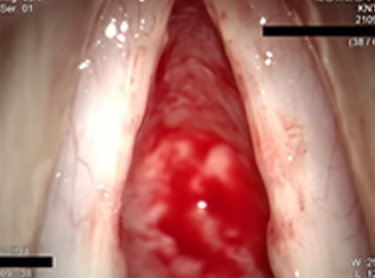

수술 1년 후 성대